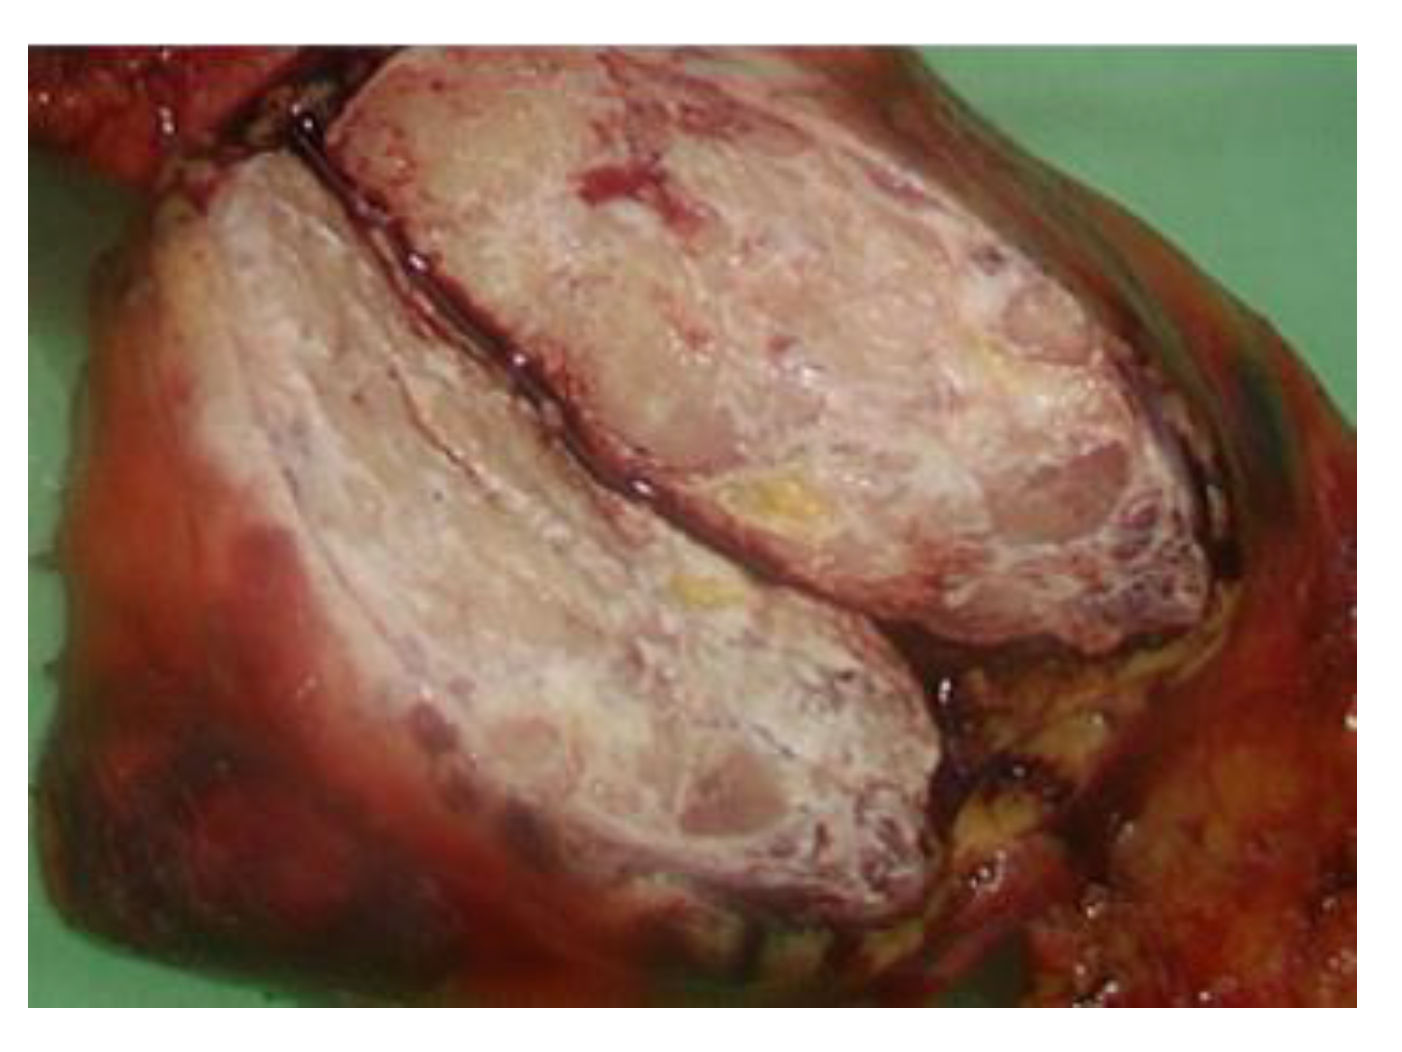

His first admission was to the division of infectious diseases. The 2019 novel coronavirus disease (COVID-19) had been excluded after repeated blood sampling and plain X-ray films of the chest. Blood tests showed a white blood cell count of 12,850 cells/mm3, hemoglobin level of 13.3 g/dL, platelet count of 490,000 cells/mm3, plasma creatinine level of 1.0 mg/dL, alanine aminotransferase (ALT) level of 79 U/L, aspartate aminotransferase (AST) level of 38 U/L, and c-reactive protein (CRP) level of 15.00 mg/L. Serum tests did not identify viral hepatitis infection. Microbiology examination of the sputum, blood, urine, and feces did not identify any pathogens. Blood sampling did not detect any autoantibodies. Physical examination did not reveal abnormal murmurs of the heart or abnormal primitive neurologic reflexes. Plain X-ray films of the chest did not show mass lesions or abnormalities in the lungs. X-ray of the major joints of all limbs did not show fracture, erosion of bones, or abnormalities of soft tissue. A technetium-99m methylene diphosphonate bone scan revealed increased uptake in the left shoulder, elbow, wrist, and ankle, and right foot and toes, which was compatible with the clinically significant arthritis noted in the physical examination (Figure 1). The patient’s fever did not respond to antibiotics for 2 weeks from the first admission. Reactive arthritis was suspected initially because no significant pathogens or autoantibodies had been identified, and sterile inflammation was suspected. The fever responded to daily systemic methylprednisolone (40 mg), and the patient was discharged 17 days after the first admission.

Figure 1. A technetium-99m methylene diphosphonate bone scan revealed increased uptake in the left shoulder, elbow, wrist, and ankle, and right foot and toes.